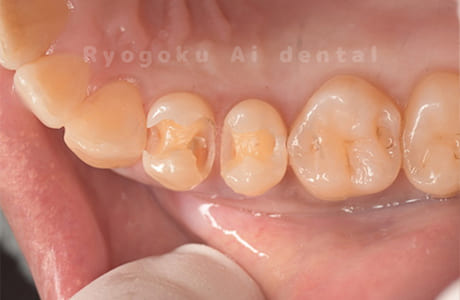

- 治療内容

- 24番ダイレクトボンディング、25番セラミックインレー修復、26・27番セラミッククラウン修復

- 387,000円

歯がしみるとのことでご来院された患者様です。銀歯の中が大きく虫歯になっておりました。セラミックの材料で再治療を行いました。